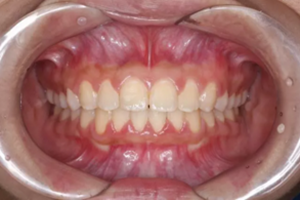

前牙正常覆合

前牙閉鎖合-深覆合

前牙正常覆蓋

前牙閉鎖合覆蓋